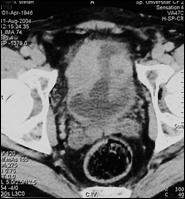

4.3. Tomografia computerizata si rezonanta magnetica nucleara

Informatiile furnizate de aceste metode moderne imagistice ridica procentajul acuratetei diagnostice pana la 85% in aprecierea infiltratiei parietovezicale a tumorilor (T) si la circa 90% pentru decelarea adenopatiei pelviene.

4.4. Rezonanta magnetica nucleara ofera cateva avantaje comparativ cu tomografia computerizata: tesutul tumoral este diferentiat mai bine de peretele vezical normal; examinarea se poate efectua in mai multe planuri; ganglionii limfatici se individualizeaza mai bine, putand fi deosebiti de vasele sanguine, si nu este necesara administrarea i.v. de substanta de contrast. In acelasi timp insa, miscarile pacientului pot induce artefacte neinterpretabile pe film, iar pacientii cu stimulatoare cardiace, clipuri vasculare metalice sau alte proteze metalice reprezinta contraindicatii pentru examenul prin RMN.

Cu toate progresele investigationale imagistice moderne, nici o tehnica de examen nu poate diferentia cu certitudine tumorile Ta de T1 sau T2 de T3a. Cel mai mare beneficiu diagnostic al tomografiei computerizate si al rezonantei magnetice nucleare consta in diferentierea corecta a tumorilor infiltrative, dar inca intra-organ (pana la T3a) de cele cu extensie extravezicale (T3b - T4a sau b). In privinta adenopatiei regionale, prin ambele metode se apreciaza ca ganglionii cu diametre mai mari de 1 cm sunt practic totdeauna invadati tumoral, in timp ce adenopatiile cu diametre mai mici considerate reactive, desi in cadrul acestora unele sunt totusi determinari neoplazice.

a. b.

c. d.

Figura 43. a,b,c,d) Imagini RMN de tumora vezicala.